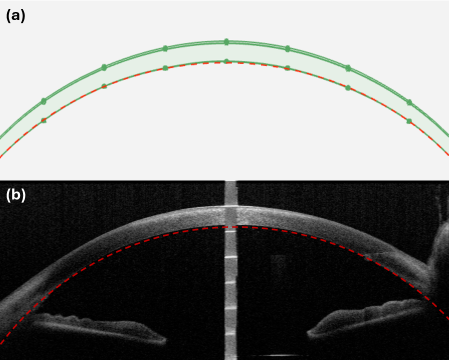

Refer to caption

Figure 1: (a) Semi-circular baseline curvature used as the first-order corneal support profile (red dashed curve). (b) Clinical corneal OCT B-scan with the fitted semi-circular baseline overlaid (red dashed curve) to illustrate dome-shape consistency. Panel (b) is from the public dataset https://doi.org/10.6084/m9.figshare.25952845[9] and was cropped and annotated for visualization.

An anatomically plausible corneal B-scan geometry with controllable variability is generated by modeling each corneal layer boundary as a smooth 2D curve along the lateral axis xx. A global baseline curvature is first defined using a semi-circular support profile,

which captures the dome-shaped corneal curvature and provides a physically interpretable first-order fit to the dome-shaped corneal boundary and is visually validated against a representative clinical B-scan in Fig. 1. A parameterized sinusoidal–Gaussian deformation is applied to the baseline surface, enabling keratoconus-like cone formation via localized steepening (Figure 2 shows an example of simulated healthy and keratoconus-like corneas). The deformation is defined as